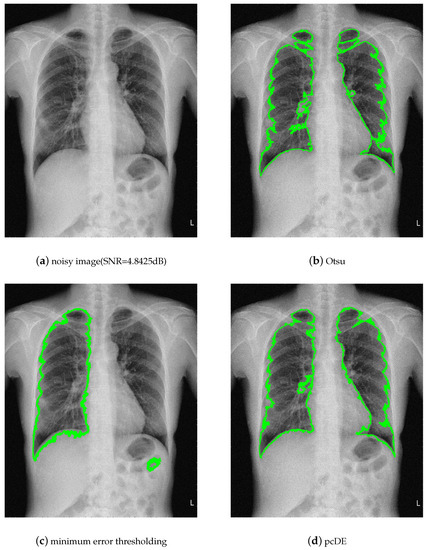

5. Case of Study: Parallel Compact Differential Evolution for Image Segmentation

- Image preprocessing. Enhance the contrast of the image to achieve better segmentation.

- Calculate the optimal threshold for image segmentation through different methods to get the binarized image.

- Use morphological methods to process images to extract targets.

- Mark target contour.

- : Represent the result of ground truth segmentation (Figure 13).

- : Represent the result of algorithm segmentation.

| Segmentation Method | Original Image | Noisy Image |

|---|---|---|

| Otsu | 0.9210 | 0.9531 |

| minimum error thresholding | 0.9732 | 0.9093 |

| pcDE | 0.9738 | 0.9684 |